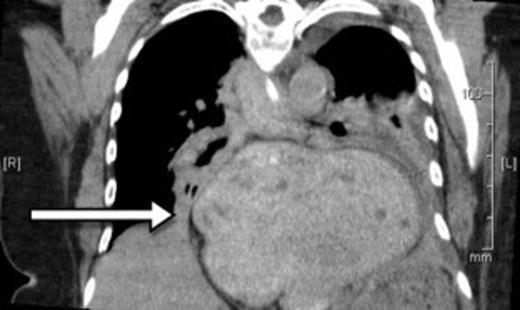

A 73-year-old Caucasian woman presented to the emergency department with 2-day history of vomiting and vague abdominal pain. Her background history included asymptomatic hiatus hernia, morbid obesity (BMI of 35.7), polymyalgia rheumatica, previous laparoscopic cholecystectomy, hypercholesterolaemia and hypertension. Regular medications included prednisone, amlodipine and cilazapril. On presentation she was tachycardic at 110 beats/min with otherwise normal vital signs. Her abdomen was generally tender but without any localised peritonism. Initial laboratory investigations on admission showed a leukocytosis (WCC of 13.8 x 109/L). Routine X-ray (figure 1) and subsequent (CT) scan (figure 2) both revealed a large strangulated paraoesophageal hernia. Radiographic changes (figure 3) were seen with gas within stomach wall, suggestive of gastric necrosis.

CT showing gas within stomach wall (arrow) suggestive of gastric necrosis